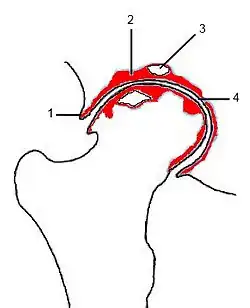

(1) (Rand-)Osteophyt

(2) subchondrale Sklerosierung

(3) Geröllzyste

(4) Gelenkspaltverschmälerung

Der Patient berichtet bei der Anamnese über Gelenkschmerzen, anschließend muss geklärt werden, bei welchen Gelegenheiten dieser Schmerz auftritt. Es folgt die klinische Untersuchung der Gelenkkontur, der Funktion, der Bandstabilität, der umgebenden Muskulatur. Dann schließt sich, je nach Erfordernis, eine bildgebende Diagnostik an, wie beispielsweise Röntgen, Computertomographie (CT) oder Magnetresonanztomographie (MRT). Zeichen einer bestehenden Arthrose sind dabei eine Verschmälerung des Gelenkspaltes, Sklerose (eine reaktive Knochenverdichtung zu beiden Seiten des Gelenkspaltes), Osteophytenbildung an den Gelenkrändern und subchondrale Zystenbildungen des gelenkbildenden Knochens, die durch feine Rissbildungen des Knorpels und Durchtritt von Gelenkflüssigkeit in die darunter liegende Knochenschicht entstehen. Eine Verschmälerung des Gelenkspalts deutet dabei auf eine Arthritis oder eine Arthrose hin, je nachdem, ob der gelenknahe Knochen verdünnt oder verdickt ist.[17]